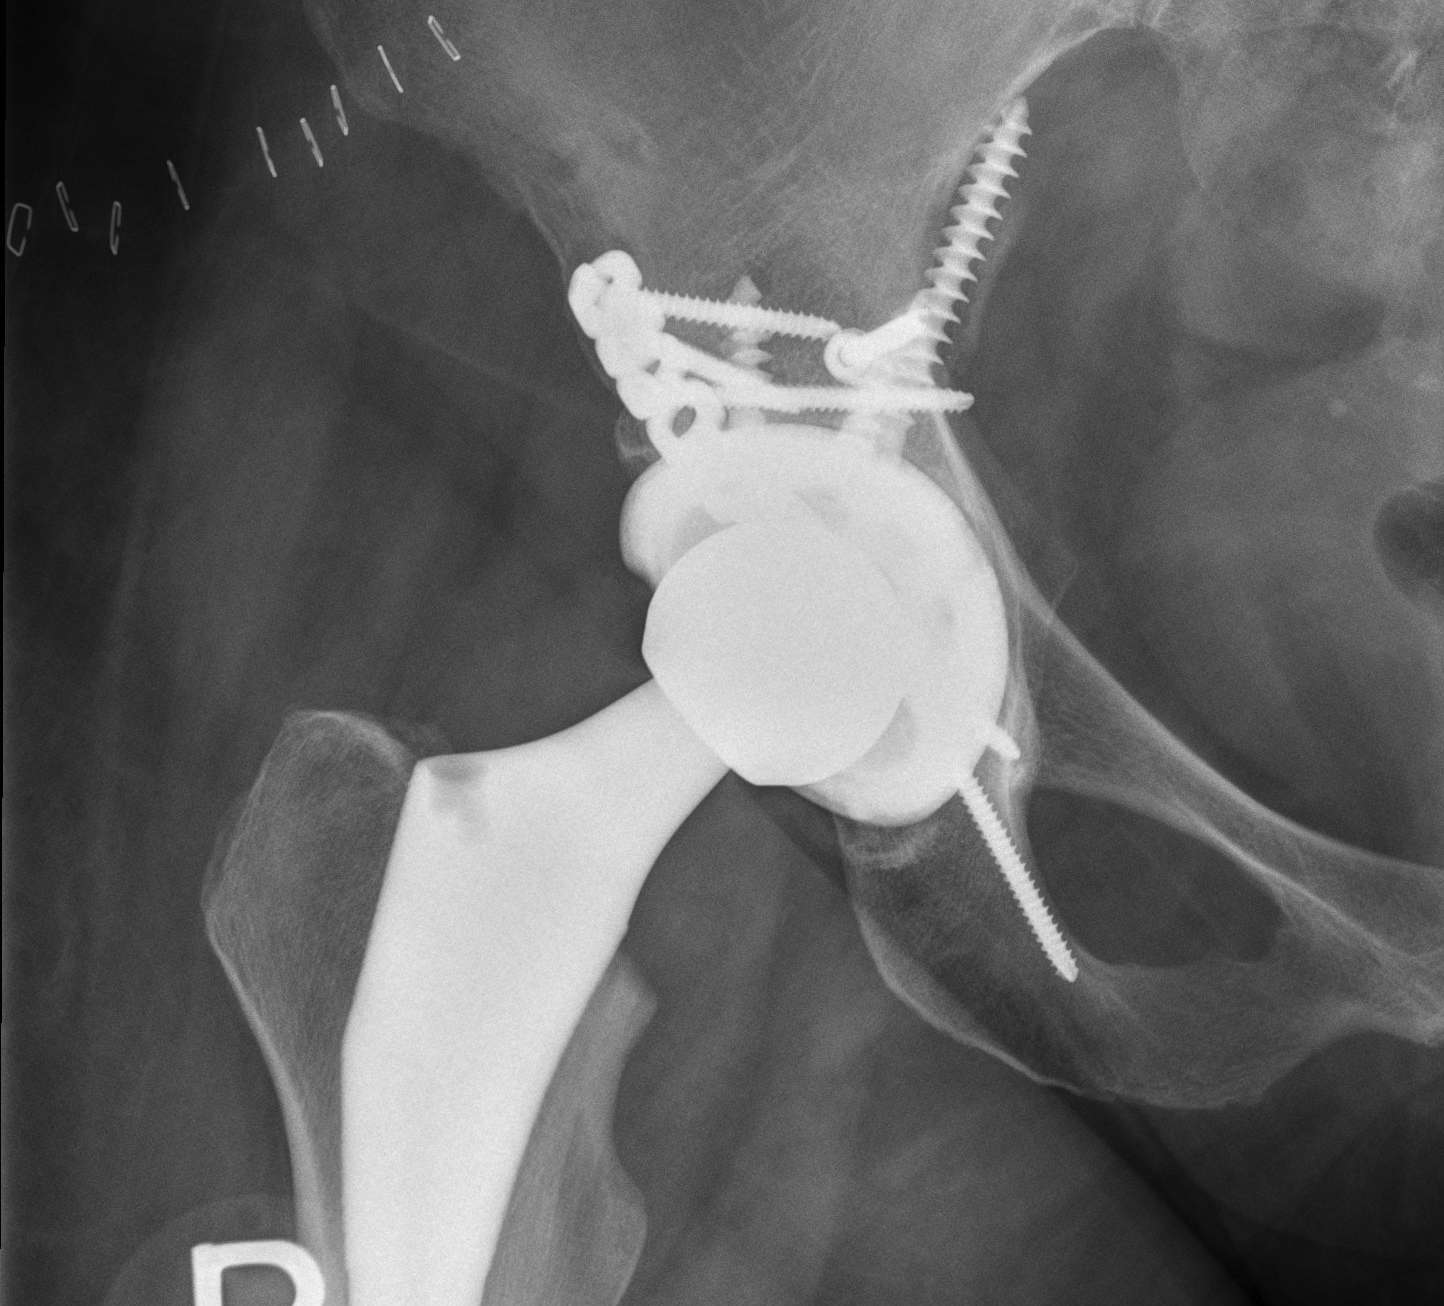

Postoperative acetabular fracture treated with double posterior plating

- plate posterior column if fractured

- screw fixation anterior column

- additional screws in cup +/- cage

- touch weight bear for period